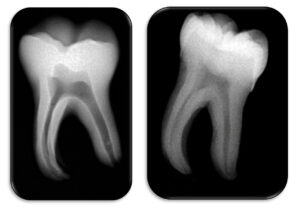

Left: 3D-printed tooth (without gradient); right: natural tooth.

The comparison highlights an accurate reproduction of the internal anatomy, particularly the pulp chamber and root canals.